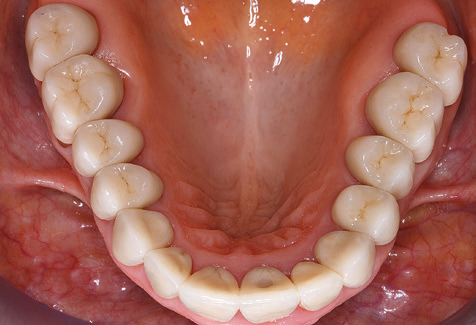

Aufgrund der bestehenden parodontalen Vorerkrankung erfolgte die unterstützende Parodontaltherapie (UPT) in den ersten Jahren in einem DreiMonatsIntervall. Dabei zeigte die Patientin eine hohe Motivation und gute Compliance. Bei den jährlich erhobenen Sondierungsbefunden zeigten sich stabile parodontale Verhältnisse mit einem BOPIndex unter fünf Prozent. Aufgrund der stabilen parodontalen Situation und der guten Mitarbeit der Patientin wurde ab dem sechsten Jahr der prothetischen Funktionsphase das Recallintervall auf halbjährlich umgestellt. Auch mit diesem veränderten Recallintervall zeigten sich bei der jeweils jährlichen Aufnahme des Parodontalstatus stabile parodontale Verhältnisse, ohne Zunahme der Sondierungstiefen und einem BOPIndex unter fünf Prozent (Abb. 2a und b).

Im Rahmen der ZehnJahresKontrolle zeigten sich keine Hinweise auf einen fortschreitenden parodontalen Attachmentverlust oder einen periimplantären Knochenverlust (Abb. 3).

Für den klinischen Langzeiterfolg des parodontal kompromittierten Patienten ist die standardisierte und regelmäßige risikoadaptierte Betreuung im Rahmen der UPT der zentrale Baustein des Behandlungserfolgs. Dies gilt in besonderer Weise für Patienten, die nach erfolgreich abgeschlossener parodontaler Sanierung mit Implantaten versorgt wurden (Abb. 11a und b).